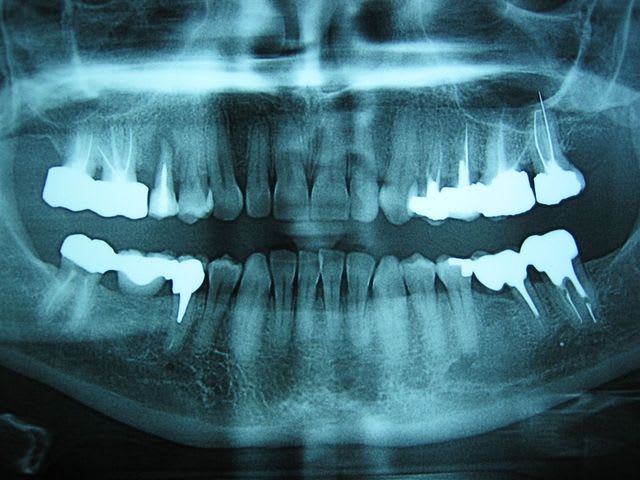

... dépassements de pâte ou de cônes d'argent ... même combat!

B - Eugenol